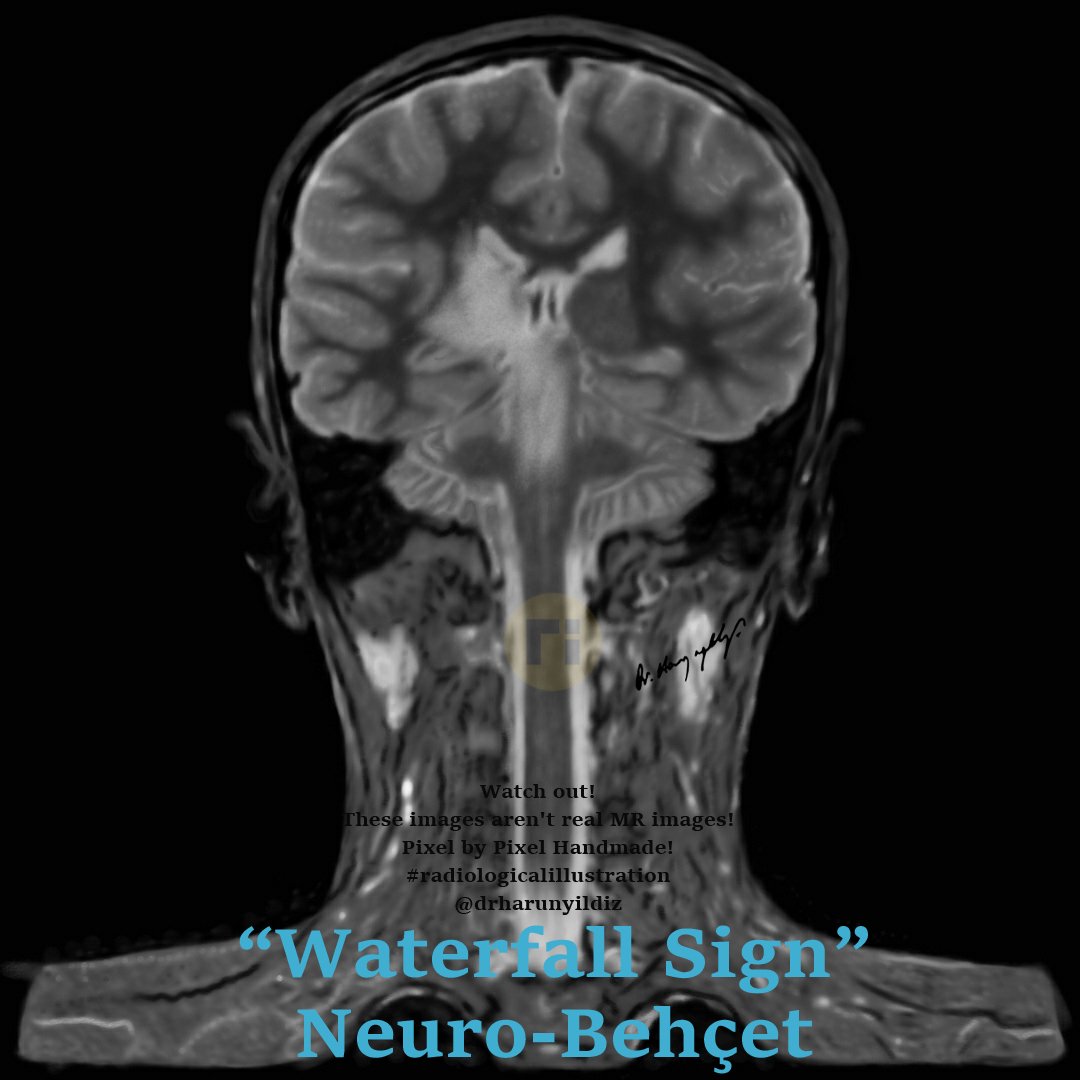

“Waterfall Sign" / Neuro-Behçet doi.org/10.1016/j.radc… ajnr.org/content/quiz/1… #radiologicalillustration ✍️ Pixel by Pixel Handmade!

drharunyildiz's tweet image. “Waterfall Sign" / Neuro-Behçet